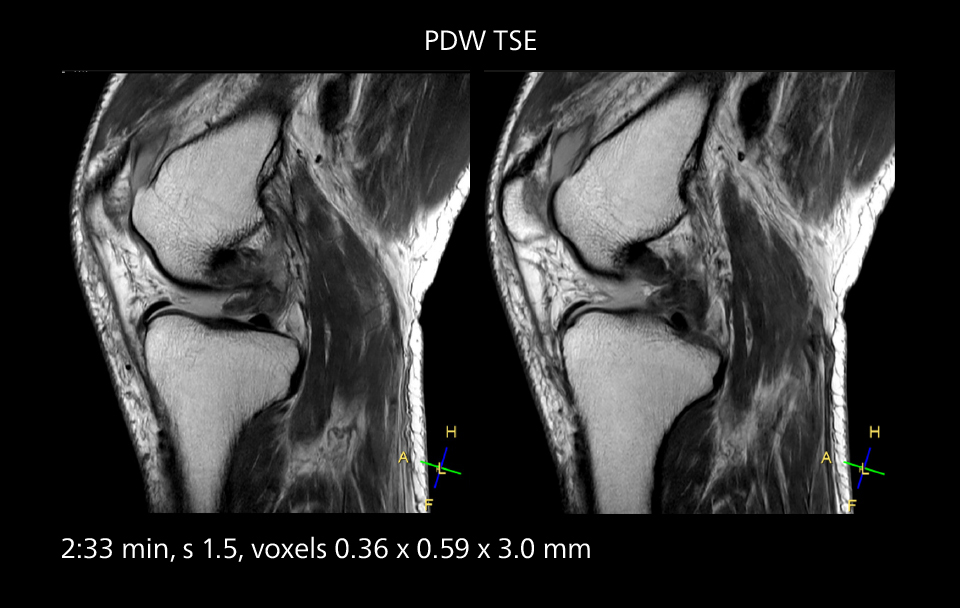

An example of increased imaging speed is in knee studies. “There is a definite scan time reduction for T2* mFFE and proton density TSE – both of these sequences benefit from much shorter repetition times,” he reports.

MRI of the knee

Images showing a posterior cruciate ligament (PCL) tear, a detached medial collateral ligament (MCL) on the tibial side and an intact anterior cruciate ligament (ACL). SmartPath to Elition X helped reduce scan time compared to previous imaging while maintaining resolution.